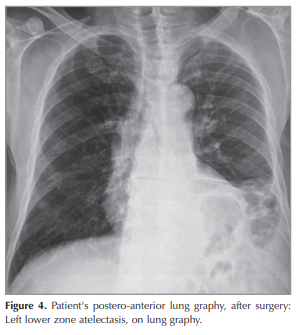

The patient is a 51-year old man, presented with shorthness of breath and cough for 1 months. Chest x-ray was normal (Figure 1). Chest CT scan showed a 30-25 mm heterogeneously enhanced mass lesion with well defined margin, In the left lower lobe of the lung (Figure 2). Bronchoscopy showed no endobronchial lesion. After the PET-CT, the patient was staged as cT2aN1M0 (Stage 2B) (Figure 3). He received video-assisted thoracoscopic surgery of left lower lobe of lung and mediastinal lymph nodes dissection ((Figure 4),(Figure 5)). His Ebv-Dna is Positive in blood tests. The pathology, immunohistochemical staining,and in situ hybridization results confirmed LELC of lung (Figure 6). Using in situ hybridization with exhibition of abundant EBV-encoded small nuclear RNA, in the majority of tumor cells is done. He received 4 cycles of induction chemotherapy with cysplatine and vinoralbine. The patient was discharged from hospital with close follow-up. No recurrence has been detected so far.

The patient is a 51-year old Turkish man, presented with shortness of breath and mild cough for 1 months. He has no chronic disease. Chest x-ray was normal (Figure 1). Chest CT scan showed a 30 × 25 mm heterogeneously enhanced mass lesion with well defined margin and lobulated contour, in the left lower lobe of the lung (Figure 2). Bronchoscopy showed no endobronchial lesion. Head and neck CT scan and nasopharyngeal fiberoscopy were performed and no obvious tumor was found. After the PET-CT, the patient was staged as cT2aN1M0 (Stage 2B), (Figure 3). He received video-assisted thoracoscopic surgery, of left lower lobe of the lung and mediastinal lymph nodes dissection ((Figure 4),(Figure 5)). His Ebv-Dna is Positive in blood tests. The pathology, immunohistochemical staining (Figure 6) and in situ hybridization results confirmed LELC of the lung. Using in situ hybridization with exhibition of abundant EBV-encoded small nuclear RNA, in the majority of tumor cells is done. Immunohistochemical staining was positive for cytokeratin (CK), a marker which was almost always positive in LELC of lung. He was discharged 10 days after the operation. He received 4 cycles of induction chemotherapy with cysplatine and vinoralbine. The patient had no postoperative complication and was discharged with the advice of chemotherapy. No recurrence has been detected so far.